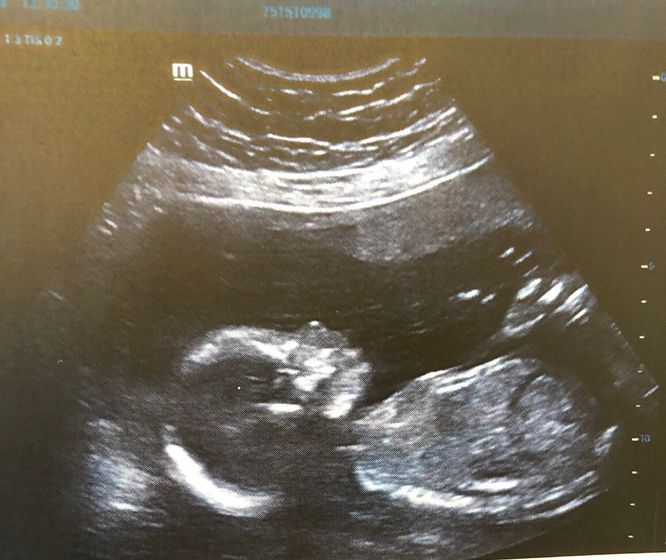

А у нас дееееевочка. Узнали только сейчас, так как живем в Китае, а тут по закону запрещено сообщать пол малыша. Наконец-то удалось вырваться в Гонконг и посмотреть кто же у нас там сидит ???? так сильно хотели девочку и вот она малышка наша ?????